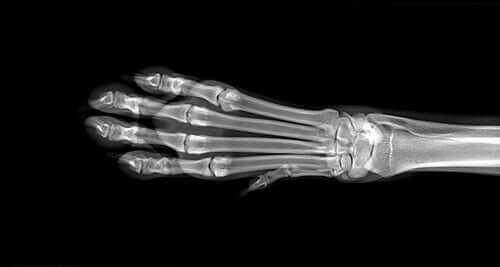

For det første vil veterinæren din utføre en rekke diagnostiske tester for å identifisere årsaken til hevelsen. Dette inkluderer blod- og urinprøver og mulige røntgen av lemmene. Dersom disse prøvene ikke viser noe avgjørende, kan det hende de vil ta en MR. Dersom de mistenker at det er osteosarkom, vil de utføre en biopsi av beinet.